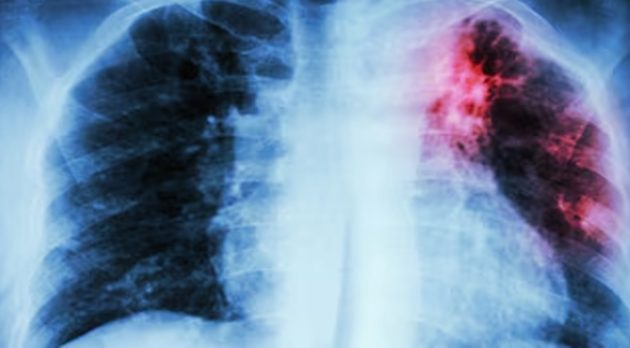

Entre las complicaciones más graves y persistentes destaca la fibrosis pulmonar poscovid, una cicatrización anómala del tejido pulmonar que transforma un órgano elástico y vital en una estructura rígida e ineficiente, reseñó Ultimas Noticias .

El especialista detalla que la arquitectura pulmonar, antes similar a una esponja suave, se vuelve comparable a una red de cuero endurecido, lo que dificulta el intercambio de oxígeno con la sangre y causa dolor en el paciente.

La detección de la enfermedad se confirma mediante tomografía computarizada de alta resolución (Tcar), donde se observan patrones característicos de “vidrio deslustrado” que evolucionan hacia opacidades reticulares y, en casos severos, el aspecto de “panal de abeja”.